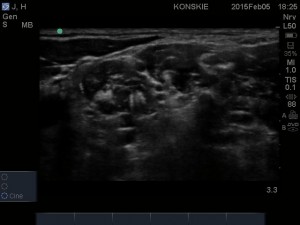

- Nerw przeponowy, splot ramienny